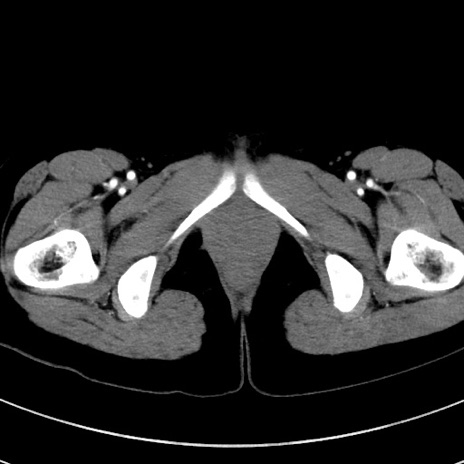

症例17(横断像)

【症例】20歳代女性

【主訴】嘔吐、下腹部痛

【現病歴】昨日夕食後に嘔吐し下腹部痛が出現。本日になっても嘔吐持続し改善しないため来院。

【身体所見】意識清明、BT 37.2℃、BP 108/67mmHg、腹部:平坦、やや硬、下腹部正中から右にかけて圧痛あり、反跳痛軽度あり、tapping pain(+)。

【データ】WBC 13600、CRP 14.94